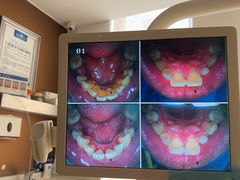

• 圣贝口腔(海淀店)

• -圣贝口腔(海淀店)